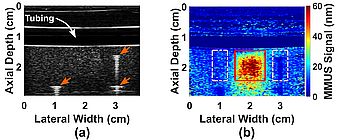

Past experiments in our lab have already shown that this method of imaging using SPIO-labeled platelets as contrast agents is possible. Oldenburg et al, 2010 showed that Optical Coherence Tomography (OCT) – an imaging method analogous to Ultrasound, but using optics rather than acoustics – showed that SPIO-platelets specifically adhered to a thrombus formed on a damaged vascular endothelium and provided contrast, compared to no contrast from that on un-damaged endothelium. Importantly, we have recently demonstrated that MMUS can sense simulated thrombus in the presence of pulsative flow (Levy et al, 2018). An MMUS image of such a model SPIO-labelled clot beneath a model thin plastic artery is shown in Figure 2.

Fig. 2. A thin plastic tube embedded in gelatin models a blood vessel passing through human tissue. Water pumps though the tube (simulating blood flow), and a cubical gelatin model thrombus containing iron oxide particles is placed below the vessel. Figure (a) shows what is seen with conventional ("B-mode") ultrasound, and figure (b) shows what is seen with MMUS. The model thrombus is only visible in the MMUS image, and it appears as a red and yellow square beneath the tube. The true location of the model thrombus (shown by the thin red outline) can be seen to align well with the detected location. More on these images may be found in our recent publication: (Levy et al, 2018).